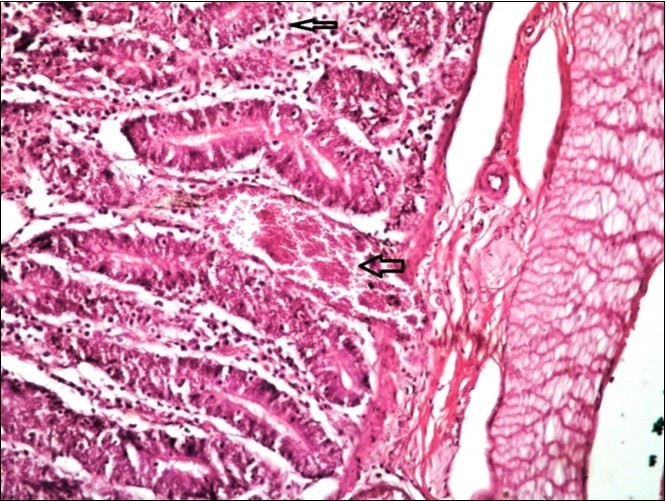

Figure 13.Small intestine (dead cattle less than 1 year old) showed hydropic degeneration, congested blood vessels, inflammatory cells (H&E, X 30).

Small intestine (dead cattle less than 1 year old) showed hydropic degeneration, congested blood vessels, inflammatory cells  (H&E, X 30).